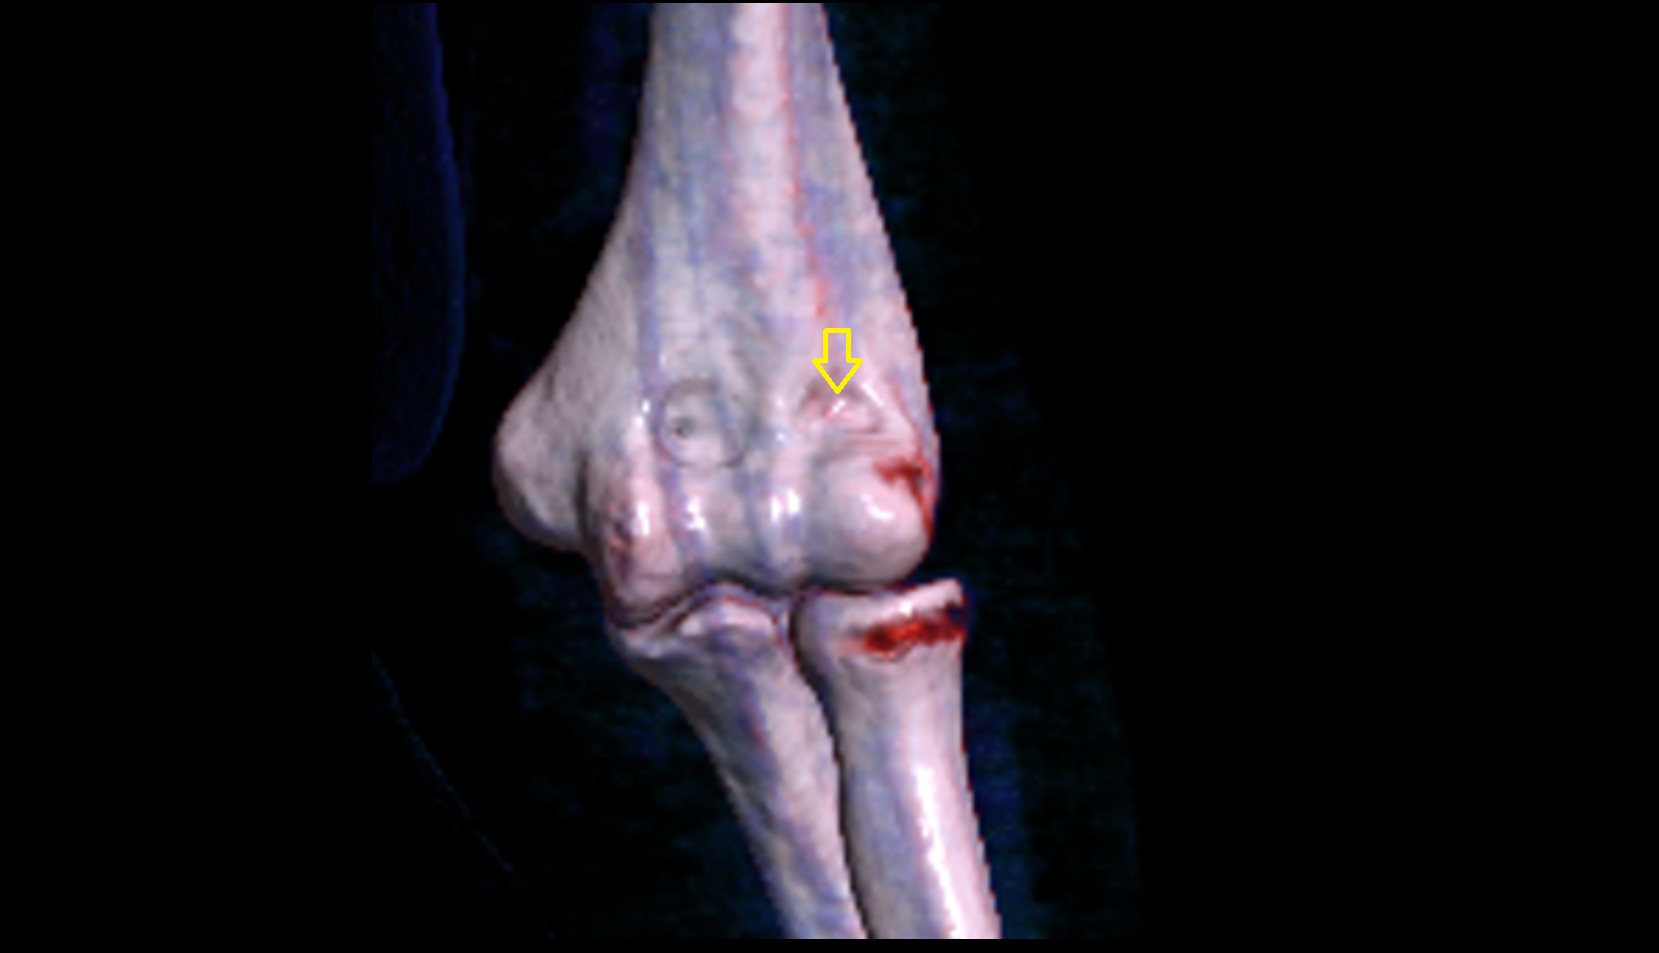

- Knee Joint